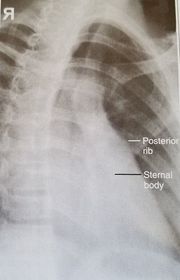

| Oblique Sternum | projection taken as LAO instead of RAO sternum is projected within the heart and scapula |

| RAO Sternum | inadequate breathing technique |

| Lateral Sternum | patient's left thorax is rotated anteriorly |

| Lateral Sternum | patient's right thorax is rotated anteriorly |

| RAO Sternum | ANATOMY: jugular notch, SC joints, sternal body, and xiphoid process CRITERIA: sternum projected within heart shadow next to vertebral column POSITIONING: pt. rotated 15-20 degrees breathing technique CR perpendicular @ midsternum (2 fingers off downside spine) |

| Lateral Sternum | ANATOMY: manubrium, sternal body, and xiphoid in profile CRITERIA: 72'' SID reduces OID arms must be behind pt's back POSITIONING: CR perpendicular @ midsternum |

| AP/PA Ribs | ANATOMY: all ribs demonstrated 1-9 for upper 8-12 for lower CRITERIA: no motion/breathing POSITIONING: AP ribs when pt c/o posterior pain PA ribs when pt c/o anterior pain CR perpendicular @ T7 |

| Oblique Ribs | CRITERIA: 45 degree oblique will shift spine away from anatomy of interest LPO/RAO = left axillary ribs RPO/LAO = right axillary ribs ribs 1-9 are seen on above diaphragm projections ribs 8-12 see on below diaphragm projections CR perpendicular @ T7 |